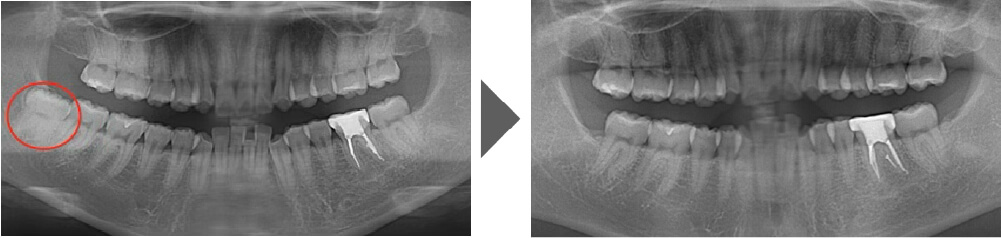

抜歯症例⑧

親知らずに歯茎が被っており、虫歯のリスクが高い状態でしたので、 抜歯することになりました。 通常は60分以上かかる難抜歯です。

【抜歯所要予約時間】

30分

(麻酔の時間があるので処置自体はもっと短いです)